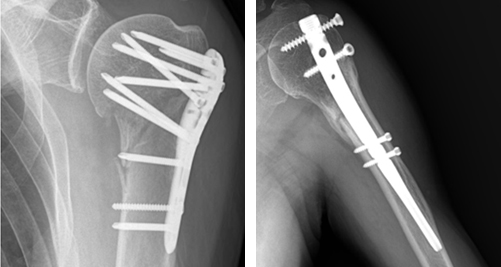

전이성 골절은 그대로 놔두면 어긋난 상태로 붙거나 잘 붙지 않을 가능성이 높습니다. 특히 근위 상완골에 붙어 있는 근육 기능이 감소하여 기능적으로 불편함이 남습니다. 따라서 많은 경우에 골편을 맞추는 수술이 필요합니다. 수술 방법으로는 골절부를 절개하는 방법과 절개하지 않고 맞추는 방법이 있습니다.골절부를 고정하는 방법으로는 핀, 쇠판, 철사 및 골수강내 정 등을 이용합니다. 간혹 골편이 4개로 분리된 심한 경우의 노인성 골절은 인공 관절 치환술을 시행하는 경우도 있습니다. 수술 방법은 골절부위를 노출시켜 어긋난 뼈를 맞추고 금속판이나 나사못으로 고정하는 방법이 널리 사용되고 있습니다. 그 외에도 골수강내핀고정법이 이용되기도 합니다.

전이성 골절에 시행되는 금속판(좌)과 골수강내 정(우)을 이용한 수술방법 위 상완골의 골절로 3개 부분이 어긋나 있는 3분 골절